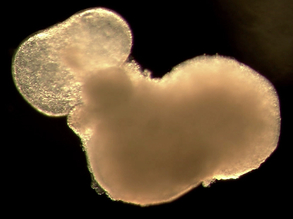

Mini Heart Organoid